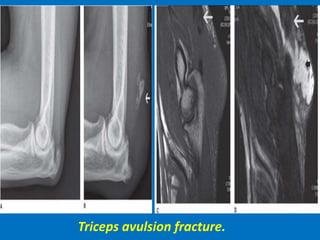

Triceps avulsion fracture.

Acute triceps tendon avulsion Tear.

Complete triceps tendon tear.

Triceps tendon tear with hemorrhage.

Avulsion of the distal triceps tendon (white arrow), with extensive overlying olecranon bursitis (black

arrows). There is cortical disruption (arrowhead) compatible with a small osseous avulsion.